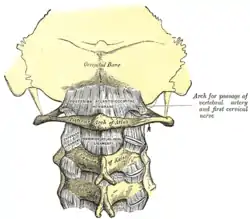

There is a pivot articulation between the odontoid process of the axis and the ring formed by the anterior arch and the transverse ligament of the atlas.

There are three atlanto-axial joints: one median and two lateral:[1]

- The median atlanto-axial joint is sometimes considered a triple joint:[2]

- one between the posterior surface of the anterior arch of atlas and the front of the odontoid process

- one between the anterior surface of the ligament and the back of the odontoid process

The dens: significant depression on the skull can push the dens into the brainstem, causing death. The dens itself is vulnerable to fracture due to trauma or ossification.

Transverse ligament: Should the transverse ligament of the atlas fail due to trauma or disease, the dens is no longer anchored and can travel up the cervical spine, causing paralysis. If it reaches the medulla death can result. Alar ligaments: stress or trauma can stretch the weaker alar ligaments, causing an increase in range of motion of approximately 30%.

Posterior atlanto-occipital membrane: genetic traits can sometimes result in ossification, turning the groove into a foramen.

A widening of the atlanto-axial joint, as measured between the posterior surface of the anterior arch of atlas and the front of the odontoid process, indicates an injury to the transverse atlantal ligament.[5] Normally, this atlanto-dental distance is less than 2 mm, sometimes a maximum of 3 mm is accepted in men and 2.5 mm in women.[5]